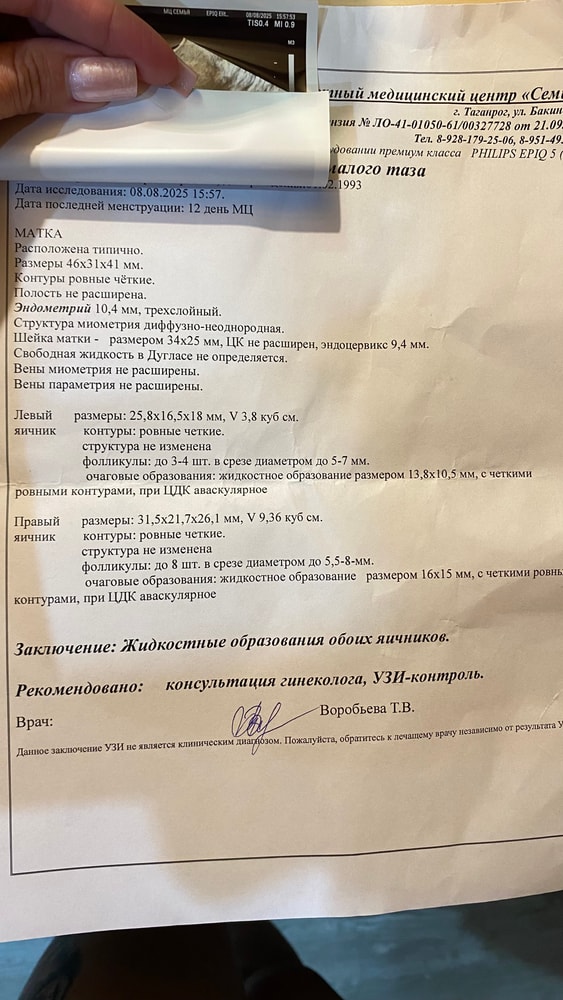

Добрый вечер)подскажите, может кто сталкивался, на фото узи на матке два пятна, узистка ничего не сказала по этому поводу, а я вот только спустя несколько дней решила рассмотреть фото. К гинекологу только через две недели попаду,а по этому поводу переживаю-вдруг беременность (хотя амг у меня 0,64) или заболевание. Узистка сказала овуляции не было и в ближайшее время не будет, вроде поздняя, хотя по дням был день когда она должна была прийти

Вероятно, кровотоки в срезе. Любая анэхогенная полость - наполненная жидкостью. Узи рассматривать по фотке совершенно неинформативно и бесполезно, скрины делают прилагая описание. Без опыта работы на узи аппарате вы совершенно ничего не поймете, как среди облаков слона искать)

Анна, на фото то, что написано в заключении